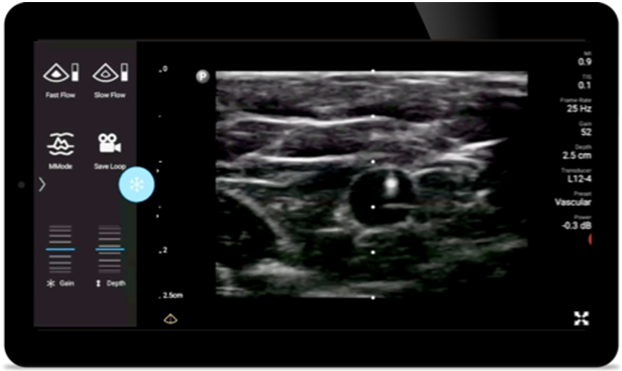

Reduce complications in needle guided procedures

Lumify handheld ultrasound for anesthesiology helps you clearly visualize border definition with your needle placement, surrounding nerves, vessels and fascial planes.